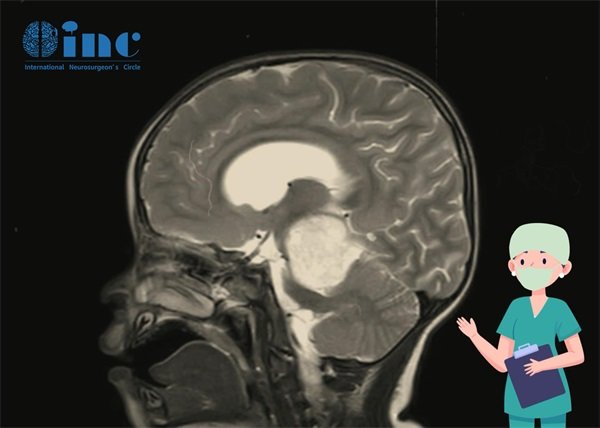

然而,脑干胶质瘤手术因其部位不同、解剖复杂性和手术风险较高,需要高度熟练的神经外科医生来实施。通常情况下,手术会在全麻下进行,通过显微镜以及其他微创技术来尽可能地切除肿瘤,并保护周围的正常脑组织不受用的问题,这个需要根据具体的医院、手术方式、手术医生和所在地区等多个因素来确定。脑干胶质瘤手术是一项复杂的手术,费用相对较高。通常包括手术费、麻醉费、住院费、药品费等方面的支出。

在中国,脑干胶质瘤手术的具体费用范围也会因为不同地区的医疗资源、医院等因素而有所差异。一般来说,手术费用可能在数万元至数十万元之间。但需要注意的是,手术费用只是治疗胶质瘤的一部分开支,患者还需要考虑到后续的康复治疗、药物费用以及可能的复发监测等方面的花费。